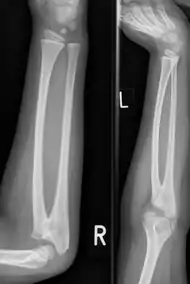

| Congenital radioulnar synostosis in a 7 year old boy | |

Radioulnar synostosis is a rare condition where there is an abnormal connection between the radius and ulna bones of the forearm.[1] This can be present at birth (congenital), when it is a result of a failure of the bones to form separately, or following an injury (post-traumatic).[2]

It typically causes restricted movement of the forearm, in particular rotation (pronation and supination), though is not usually painful unless it causes subluxation of the radial head.[1] It can be associated with dislocation of the radial head which leads to limited elbow extension.[2]